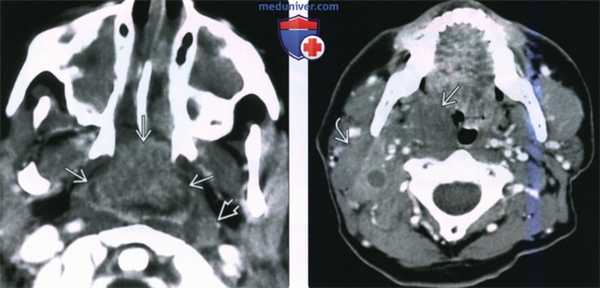

(Слева) При КТ с КУ в аксиальной проекции у ребенка со СПИД в области глоточной миндалины определяется крупная неходжкинская лимфома, неоднородно накапливающая контраст. Обратите внимание на увеличенный лимфоузел в заглоточном пространстве слева и на практически полную обструкцию просвета носоглотки. Полость носа и верхнечелюстные пазухи с обеих сторон заполнены доброкачественным секретом.

(Справа) При КТ с КУ в аксиальной проекции визуализируется мультифокальная неходжкинская лимфома с вовлечением правой небной миндалины, а также группа спаянных лимфоузлов II уровня. Шейная аденопатия встречается в 50% случаев неходжкинских лимфом слизистого окологлоточного пространства.

2. КТ при неходжкинской лимфоме слизистого пространства глотки:

• КТ с КУ:

о Опухоль крупных размеров, заполняющая просвет дыхательных путей и минимально накапливающая контраст:

- Часто не распространяется в окружающие пространства

о В 50% случаев поражаются лимфоузлы:

- Лимфоузлы обычно имеют большие размеры > 2 см без признаков некроза

- Иногда в центре обнаруживается зона некроза, особенно в случае лимфом высокой степени злокачественности:

Особенно у пациентов с ВИЧ